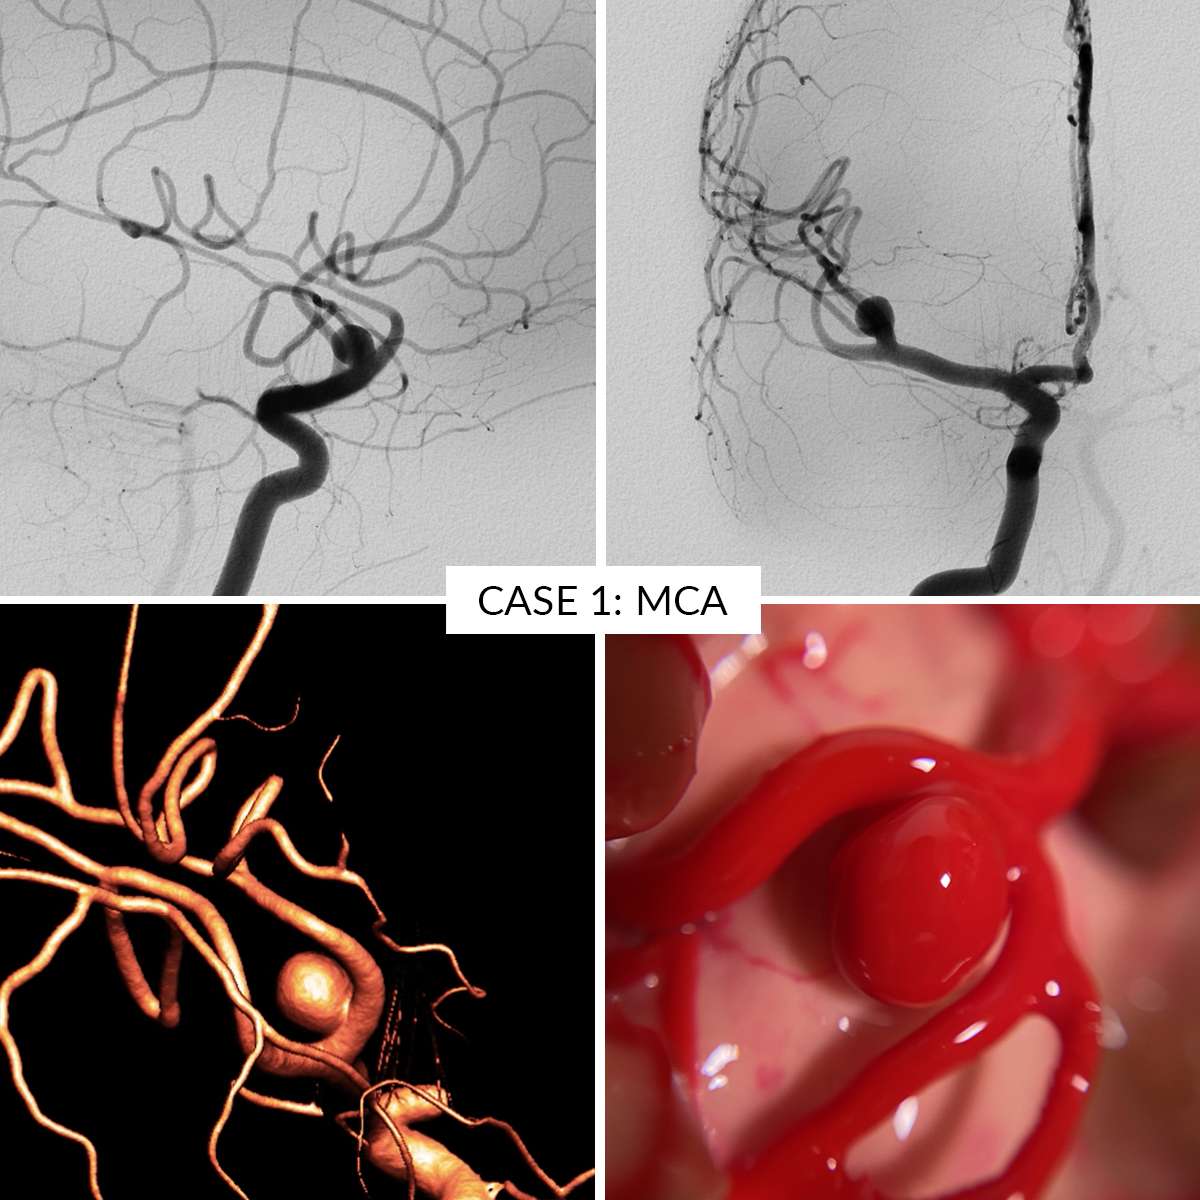

Case 5 : Posterior Communicating Artery

- Case 5: Posterior Communicating Artery